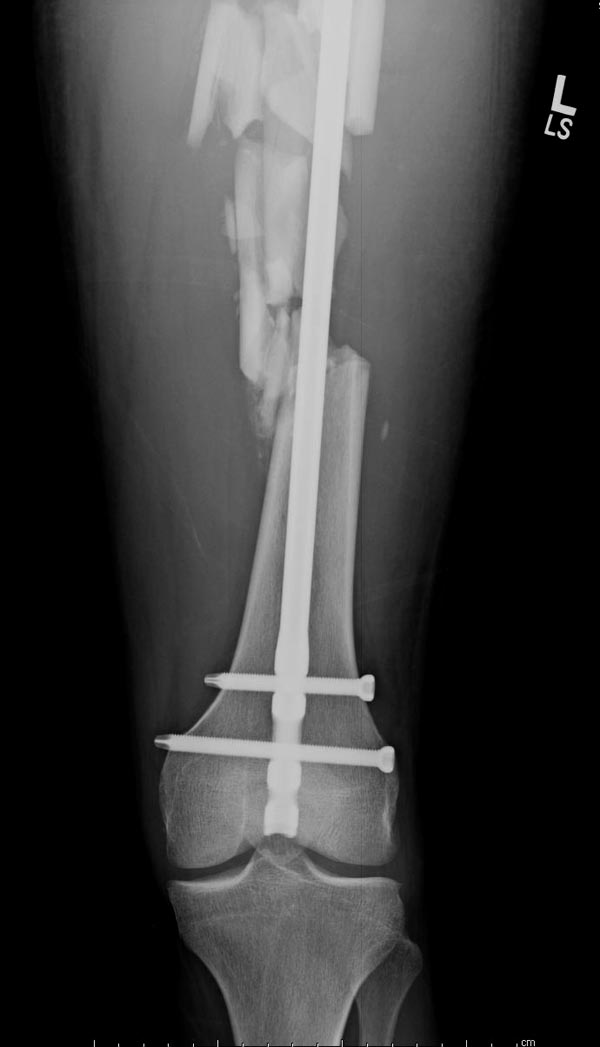

Здесь выставлен ренгенограммы больного, ему 21, травму получил в

результате высокоскоростной погони на украденной машине, которая

закончилась смертью трех остальных“боевых комрадов”. Начатую коллегой

открытую операцию на шейке пришлось закончить мне, установкой винтов и

ретроградной фиксацией бедра. Выписка в обычное сроки и наблюдался

амбулаторно. Каждый раз напоминали о возможности осложнений ввиде

несращения! По истечению 4 месяцев появились признаки варусной

деформации. На СТ срезах несращение шейки и бедра. Риминг, замена на

более толстый гвоздь и вальгусная остеотомия.